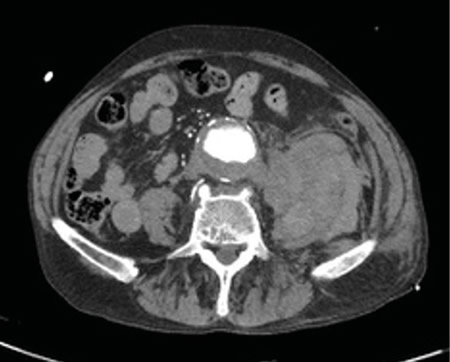

No es solo dolor lumbar: manifestación atípica del aneurisma de aorta

Not just low back pain: atypical manifestation of aortic aneurysm

La rotura de aneurisma de aorta supone el síntoma principal en hasta un 25 % de los casos de la patología de aneurisma de aorta, que constituye una entidad potencialmente mortal. También puede aparecer con menor prevalencia como lumbalgia, coxalgia e, incluso, gonalgia, no comentándolo como dolor vertebral o neuropático, sino como irritación a nivel de psoas ilíaco como primera sintomatología.

Se estima que solo en un 50 % de los casos aparece la triada clásica del aneurisma, por lo que es necesario tener un alto nivel de alerta para sospecharlo, ya que la hipovolemia puede estar contenida por un hematoma peritoneal.

Figura 2